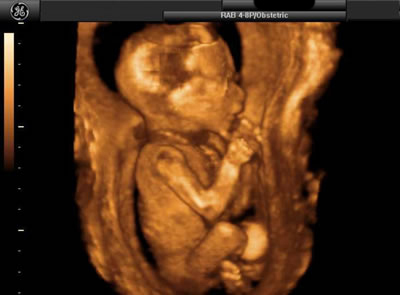

В современной медицине появилось трёхмерное УЗИ. Оно становится очень популярным и желанным методом исследования у будущих родителей. Изображение при таком УЗИ очень объёмно и гораздо нагляднее, чем плоская картинка.

Во время проведения УЗИ вы сможете первый раз увидеть своего будущего ребёнка. Я уверена, что эта самая первая встреча запомниться вам навсегда.